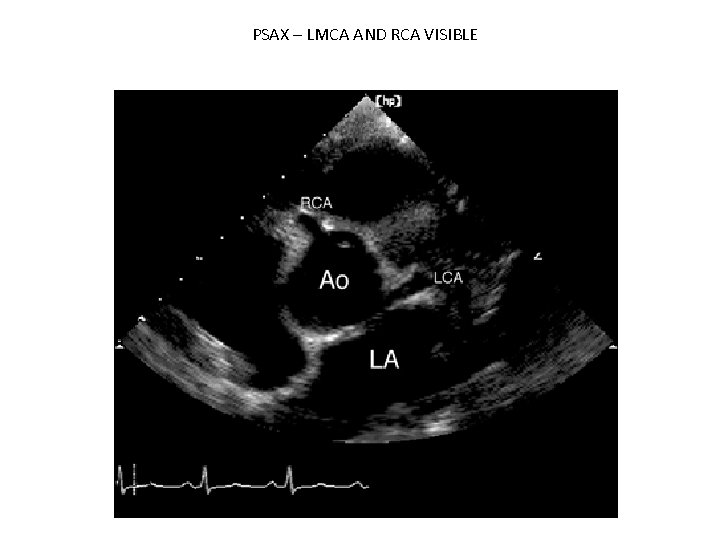

PSAX – LMCA AND RCA VISIBLE